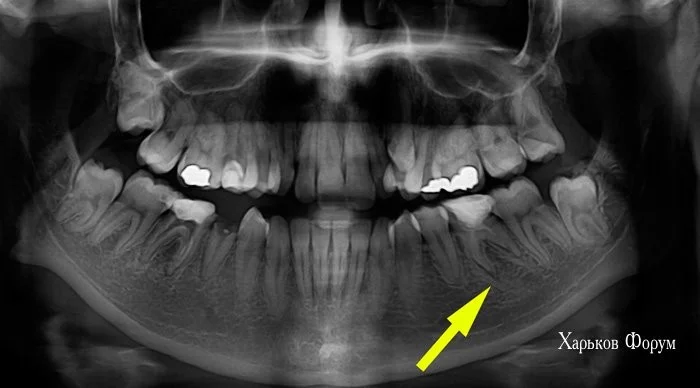

3. У Вас есть скученное положение зубов и дефицит места более 7 мм. А это железобетонное показание для лечения с удалением. Вы зря не взяли модели челюстей ДО лечения, для своего нового доктора! Они бы ему пригодились. Возможно, будут полезны фото

894a479df6110b7bc7b53.webp

ab37dc3d75222cee1.webp

Внимание! внимание! Если Вы будете расширять челюсть, то не удастся создать достаточно места для имплантов и когда будут устанавливать импланты, обязательно повредят корни двух соседних зубов. Рекомендую консультироваться еще у других врачей. Чтобы не получилось так, что мы тратили Ваше время по 15 минут в комнате ожидания, а Вы потратите год на расширение и это окажется напрасно.

План лечения включал удаление только двух премоляров на верхней челюсти. На нижней челюсти мы не предлагали удалять зуб мудрости, так как у Вас в очень плохом состоянии первый моляр. Именно поэтому постоянно делали снимок этого зуба. Боюсь, что он не простоит долго и будет уже минус 6-й и 8-й зуб.

Панорамный снимок ДО лечения прилагаю.